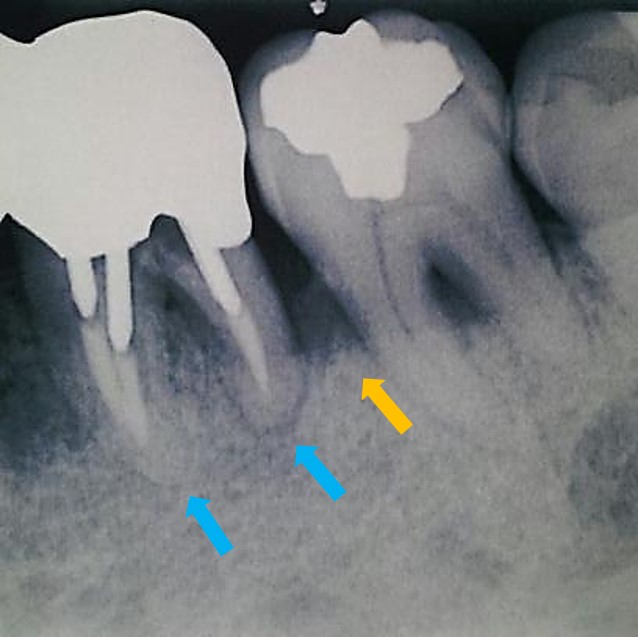

オレンジ矢印から9mmの歯周ポケットがあり、また青矢印部分に根尖病巣が認められます。

オレンジ矢印の部分に骨再生が認められ、歯周ポケットも9mmから3mmに改善しました。また根尖部透過像(根尖病巣:青矢印)も改善しています。